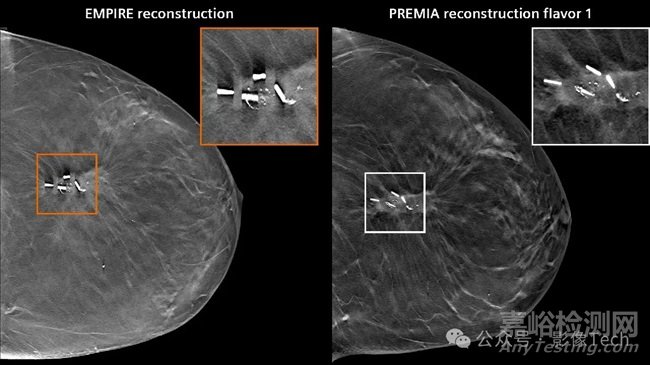

Mammomat B.brilliant結(jié)合了廣角層析成像、新型探測器、全新開發(fā)的 Flying Focus Spot 管和 Premia AI 重建技術(shù),以提高圖像質(zhì)量。

這是 Flying Focus Spot 技術(shù)首次應(yīng)用于乳腺X線攝影,該技術(shù)可以防止層析成像過程中X 射線管高速移動而造成的圖像模糊效果。即使在非常高的掃描速度下,也能產(chǎn)生清晰的3D圖像。

▲斷層合成中的偽影減少(圖片源自官網(wǎng))

在層析成像中,X 射線管圍繞乳腺繞圈移動,這與傳統(tǒng)的乳腺X線檢查不同,因?yàn)樵趥鹘y(tǒng)檢查時(shí),X 射線管是保持靜止來創(chuàng)建三維圖像的。

這款產(chǎn)品做到了市場上最快的廣角層析成像,能在盡可能短的時(shí)間內(nèi)創(chuàng)建具有高深度分辨率的 3D 圖像。這種方式可以高精度地識別乳腺組織中的異常和微鈣化。